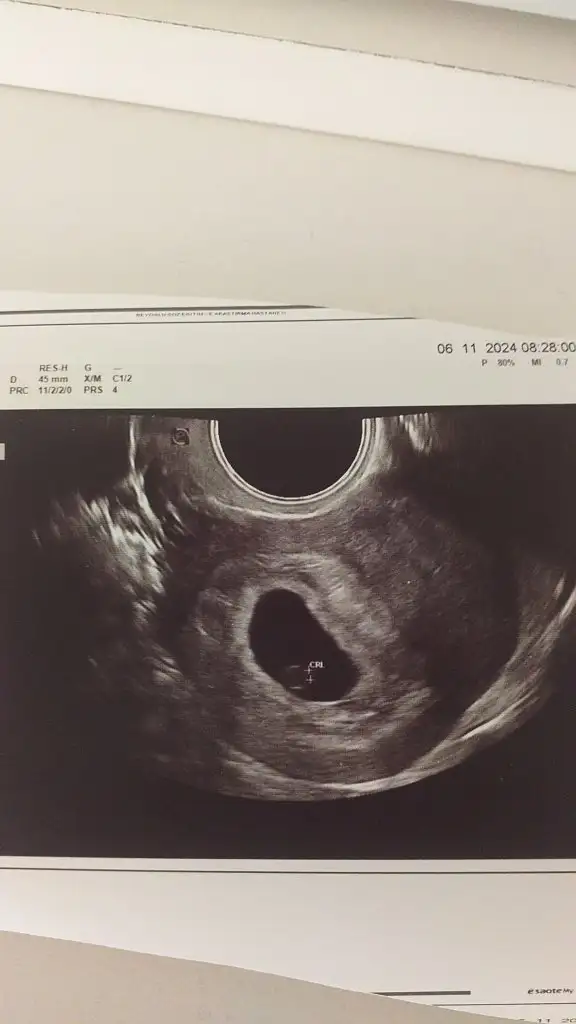

İlk çocugum ve merak ediyorum yorumlarmısınız vajinal usg

Eklentiler

• IMG-20241106-WA0001.webp